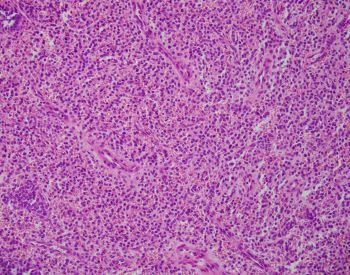

Sections show large polypoid, densely cellular fragments of endometrial stroma composed of bland cells that are small and uniform, resembling proliferative-type endometrial stroma. Admixed within this stroma are sex cord-like elements, arranged in cords, trabeculae, and retiform patterns. Endometrial stromal nodules are rare tumors. They can display a number of different histologic variants, including sex cord-like elements (as in this case), smooth muscle, endometrioid glandular elements, and myxoid/fibroblastic. A characteristic network of arterioles around which neoplastic cells often whorl is distinctive as well. A diagnosis of an endometrial stromal nodule can only be definitively made after ensuring there is no myometrial or lymphovascular invasion, and often this requires a resection rather than just a biopsy. This brings up an important differential: low-grade endometrial stromal sarcoma, as invasion renders the diagnosis of sarcoma. So, it is best to defer a definitive diagnosis to a resection specimen. Both nodules and sarcomas have similar histologic features, including sex cord-like elements. Both are also characterized by a t(7;17)(p15;q21) translocation resulting in JAZF1-SUZ12 fusion (there are others, but this is the most common).

Uterine tumor resembling ovarian sex cord tumor is also in consideration. However, the presence of endometrial stroma excludes this diagnosis. An endometrial polyp could come under the differential here as well, given the large polypoid fragments and larger, thick-walled blood vessels. The important diagnostic feature lacking in this case for a polyp are branched or cystically dilated endometrial glands within an altered, fibrotic stroma. The presence of sex cord-like elements really excludes the possibility of a cellular leiomyoma, but stromal tumors and uterine smooth muscle tumors (ie leiomyomas) can have overlap. Features favoring a cellular leiomyoma include prominent thick-walled blood vessels and cleft-like spaces.